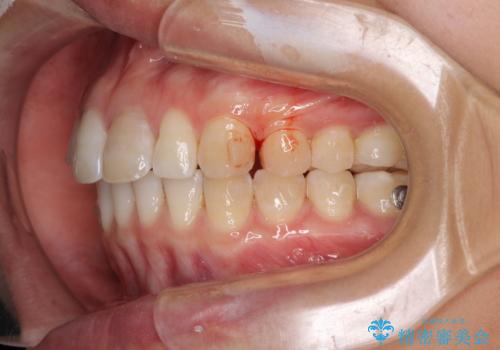

- 変色した前歯と突出した口元を気にして来院された患者様です。

口元の突出感はインビザラインにより歯列を整え、その後に、前歯をオーダーメイドタイプのオールセラミッククラウンにて補綴治療することとしました。

長時間のマウスピース装着と、患者様自身でのゴムかけに協力いただき、口元の突出感をしっかりと改善することができました。

前歯のオールセラミッククラウンもまるで本物の歯のように仕上がり、患者様には大変満足していただきました。